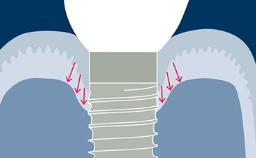

Prosthodontic Planning and Procedures

Abutment Selection for Fixed Dental Prostheses

Learning Module